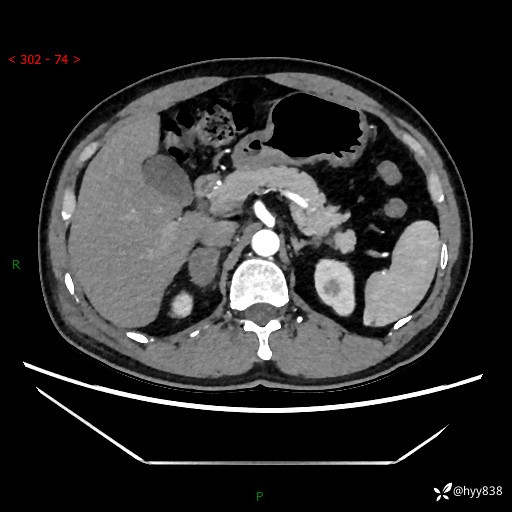

现病史:患者9月4日摔伤在深圳市宝安区中心医院行CT检查提示右侧肾上腺区结节(38*27mm),复查B超提示右侧肾上腺区可见一61*24mm异常低回声团,建议进一步检查。进一步完善增强CT后提示:右侧肾上腺区肿块及周围渗出改变,大致同前,考虑肾上腺腺瘤,不除外瘤内出血可能,否认阵发性头晕、头痛、出汗、乏力等不适,门诊以“ 右侧肾上腺肿瘤”收入住院。 起病来,患者精神、食欲、睡眠可,大便通畅,小便如上述,体力体重无明显改变。

肾上腺CT平扫

增强(动脉期+静脉期)